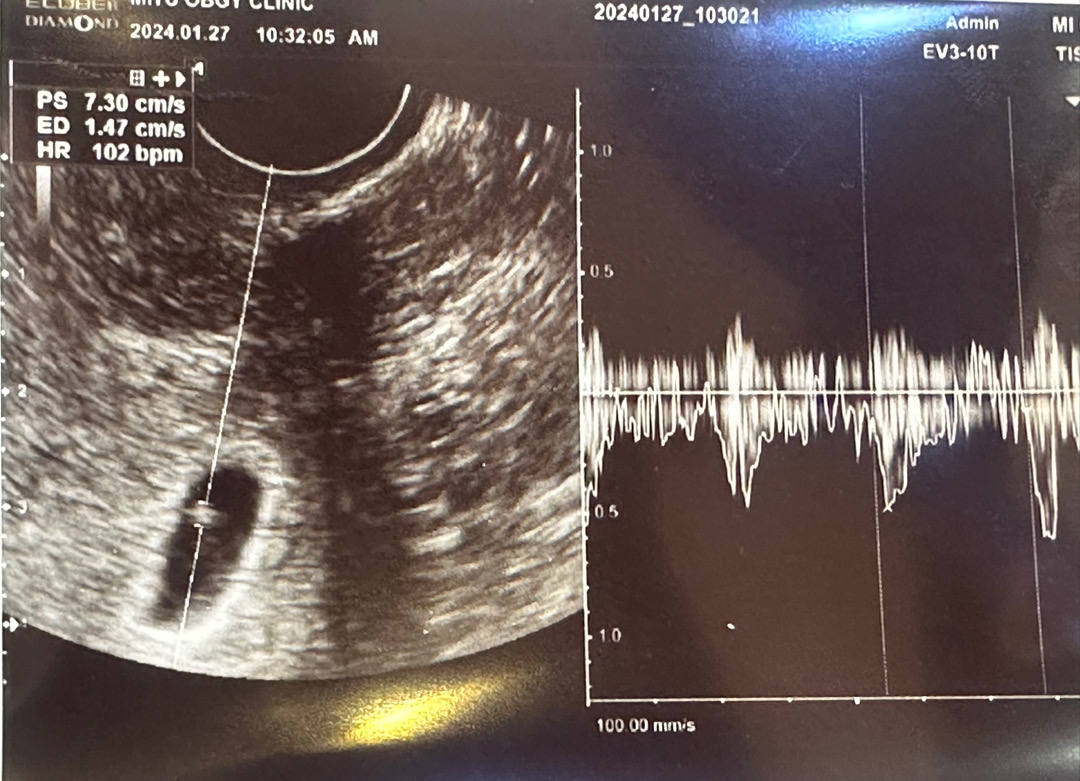

저는 5주5일에 난황에 심장소리 들었어요 ! 예정일보다 2일 줄었어요

6주3일차 되는날 별 기대없이 건강하기만했음 하는 마음으로 난황보러갔는데 ㅠㅠ 뜻밖에 심장소리까지 듣고왔어요!! 순간 오잉?! 하는 기분에 눈물도 안났지만 너무너무너무너무 행복하네요 ㅎㅎㅎ 행복한 와중에 선생님이 6주 3일차였는데 6주 1일로 뜬다구 이주뒤에 올때 다시 보자하시더라구요 ㅠㅠ 밍.. 주수바뀌시는분들도 계시나요?

저도 심장소리 들을때 아기사이즈재고 2일정도 밀렸어요! 일주일까진 괜찮다하더라구요 ㅎㅎ 6주2일에 0.36으로 6주0일로 밀리고 바뀐주수로 6주 6일에가니까 0.87로 잘 크고 있었어요!너무 걱정마세요😍💕